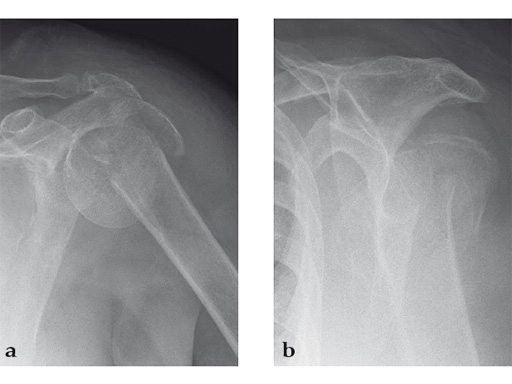

Case 2: Three-part valgus displaced fracture of the proximal humerus in a 63-year-old man.

The tuberosities have been reduced and fixed using intertubercular sutures (Fig 4). To reconstruct the medial support a calcar screw has been used. This determines the height of the nail. Therefore a 1 cm end cap has been used to get support for the proximal end of the nail in the part of the bone with the best bone quality.